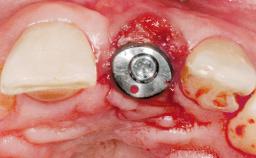

Late Placement of an Implant in a Maxillary Left Central Incisor Site

A 30-year-old female patient had lost tooth 21 and was referred to our clinic for consultation and treatment. Due to advanced apical infection, tooth 21 had been extracted two months earlier at another clinic and an acrylic-resin tooth had been bonded to the adjacent teeth. The patient desired implant treatment to avoid any damage to the adjacent natural teeth. While the patient had no history of any systemic disorder, she was a heavy smoker and exhibited medium to advanced periodontitis in the entire jaw. After the initial treatment to achieve a pocket probing depth of less than 4 mm and no bleeding on probing, a decrease in the height of the papillae mesial and distal to the extraction site and overall gingival recession were observed.